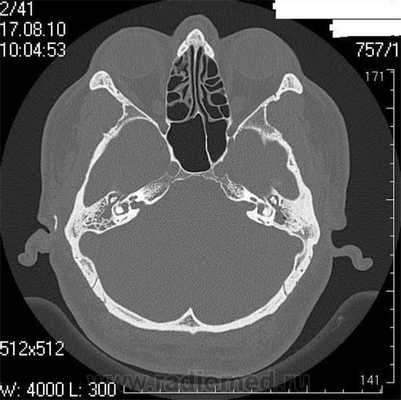

Что покажет КТ височных костей, как делают, подготовка и противопоказания

Височная кость является важной анатомической структурой - она участвует в формировании черепной коробки, здесь расположен слуховой аппарат, проходят крупные нервы и артерии. Обычные методы диагностики, такие как рентгенография или УЗИ, зачастую не позволяют диагностировать патологические изменения в этой области. КТ височных костей − более точное исследование, которое дает возможность выявлять заболевания на ранней стадии.

Что покажет КТ височных костей

Во время КТ получают послойные снимки височной кости и окружающих тканей в трех плоскостях. Толщина среза составляет всего несколько миллиметров, что позволяет врачу-рентгенологу рассмотреть не только все анатомические образования, но и минимальные патологические изменения.

На полученных снимках хорошо видны следующие структуры:

пирамида височной кости;

ячейки и антрум сосцевидного отростка;

улитка, преддверие, передний и задний полукружный каналы;

слуховые косточки среднего уха;

стенки наружного слухового прохода;

Снимок (томограмма) височных костей в осевой проекции

С помощью КТ височных костей можно выявить любые заболевания воспалительного, травматического, опухолевого характера. Метод применяется для диагностики следующих патологий: